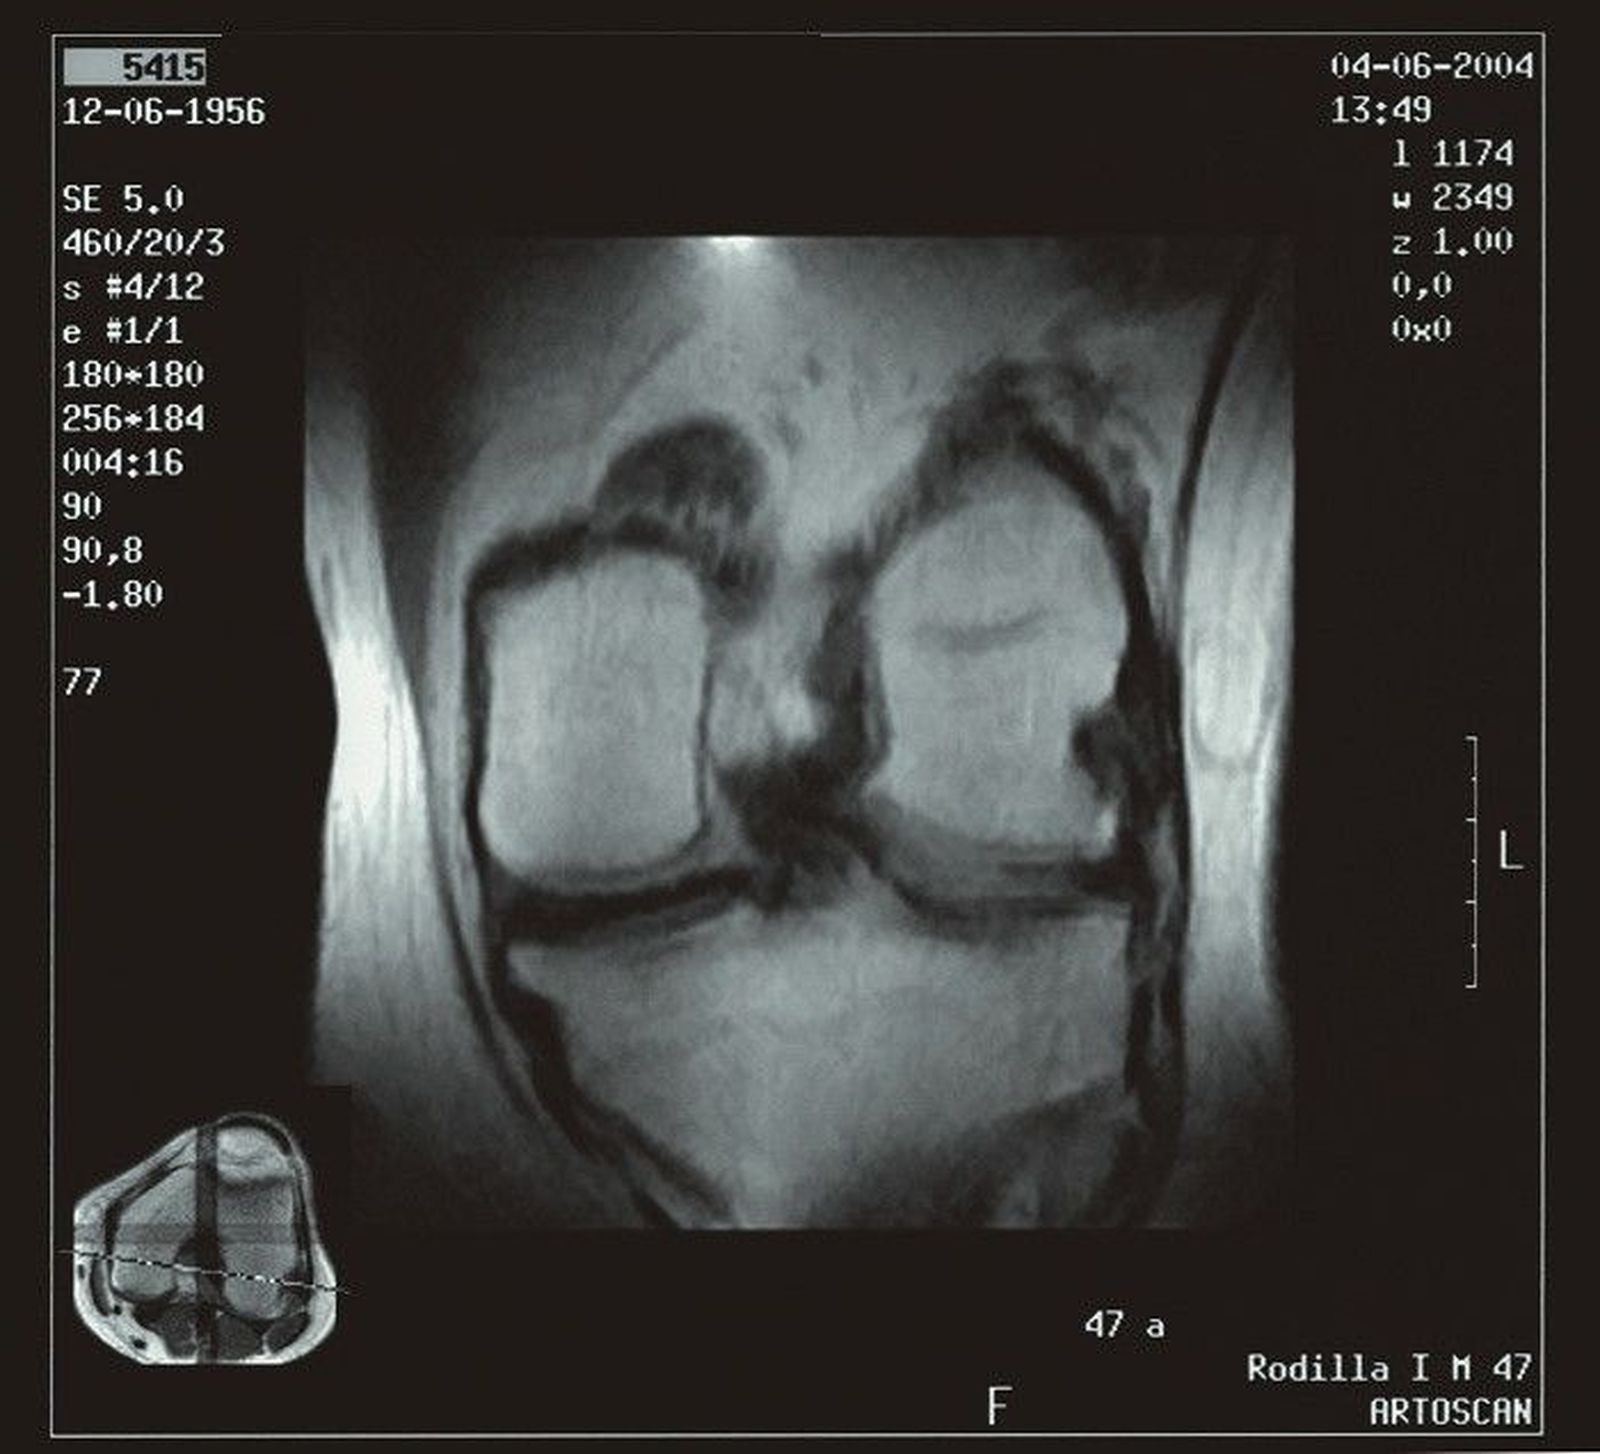

La artrosis es la forma más común de artritis, que afecta a más de 500 millones de personas en todo el mundo. Se produce con mayor frecuencia en las manos, las caderas y las rodillas. En las personas con artrosis, el cartílago que amortigua la articulación se desgasta gradualmente. La artritis suele ir acompañada de una inflamación, o hinchazón, de la articulación, que puede ser dolorosa.

Para el estudio, se incluyeron 277 participantes de la cohorte de la Iniciativa de artrosis con artrosis de moderada a grave y tratamiento sostenido con AINE durante al menos un año entre el inicio y el seguimiento de cuatro años, y se compararon con un grupo de 793 participantes de control que no fueron tratados con AINE. Todos los participantes se sometieron a una resonancia magnética de 3T de la rodilla inicialmente y después de cuatro años. Las imágenes se puntuaron en busca de biomarcadores de inflamación.

El grosor del cartílago, la composición y otras mediciones de la IRM sirvieron como biomarcadores no invasivos para evaluar la progresión de la artritis.